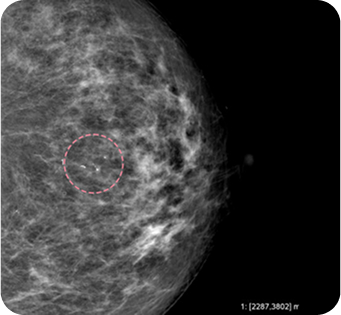

유방 섬유선종은 20~30대 젊은 여성에게 흔히 발생하는 양성 종양 으로, 대체로 위험성이 크지 않습니다. 하지만 드물게 악성으로 진행하는 경우가 있고 환자분께서 가족력으로 인한 불안을 느끼셔서 이번 사례에서는 예방적 차원에서 제거를 시행했습니다. 수술은 어렵지 않게 진행되었고, 1년 후 검사에서도 반흔 외에 재발 없이 깨끗한 결과를 확인할 수 있었습니다.